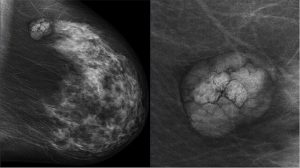

L’hématurie, qu’elle soit visible à l’œil nu ou uniquement au microscope, constitue unsymptôme à ne pas négliger. Derrière cette présence de sang dans les urines peuvent secacher des pathologies bénignes comme des affections plus graves, notamment tumorales.Le rôle de l’imagerie médicale est alors central, tant pour identifier l’origine du saignementque...